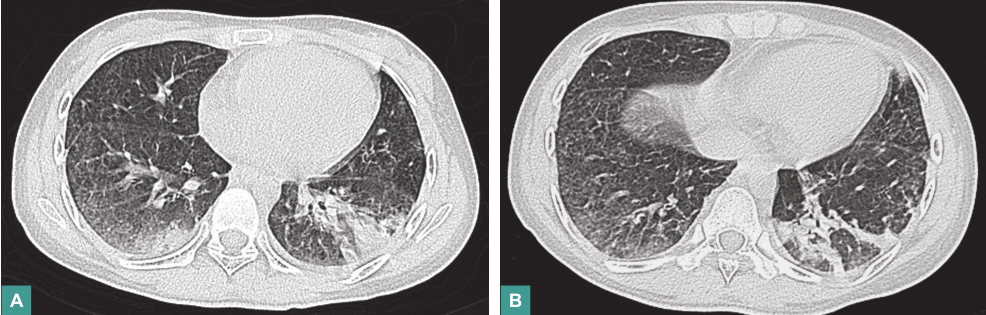

(2)影像学检查

腹部B超示盆腔少量积液;心脏彩超未见异常;胸部CT示双肺弥漫性斑片状、条索状密度增高影,边缘模糊(图1)。

图1 胸部CT表现

4.影像学检查

3.呼吸系统

SLE的肺部病变按发生率依次为胸膜炎/胸腔积液、间质性肺炎、肺动脉高压、小气道病变、急性狼疮肺炎、肺出血、肺挛缩综合征、肺栓塞等,常并存感染。本例患者胸部CT提示肺部弥漫性病变,暂无法鉴别其性质,可在治疗SLE的同时,积极抗感染,并密切随诊肺部情况。

复查胸部CT:肺部病灶较前有所吸收(图4)。

图4 胸部CT表现